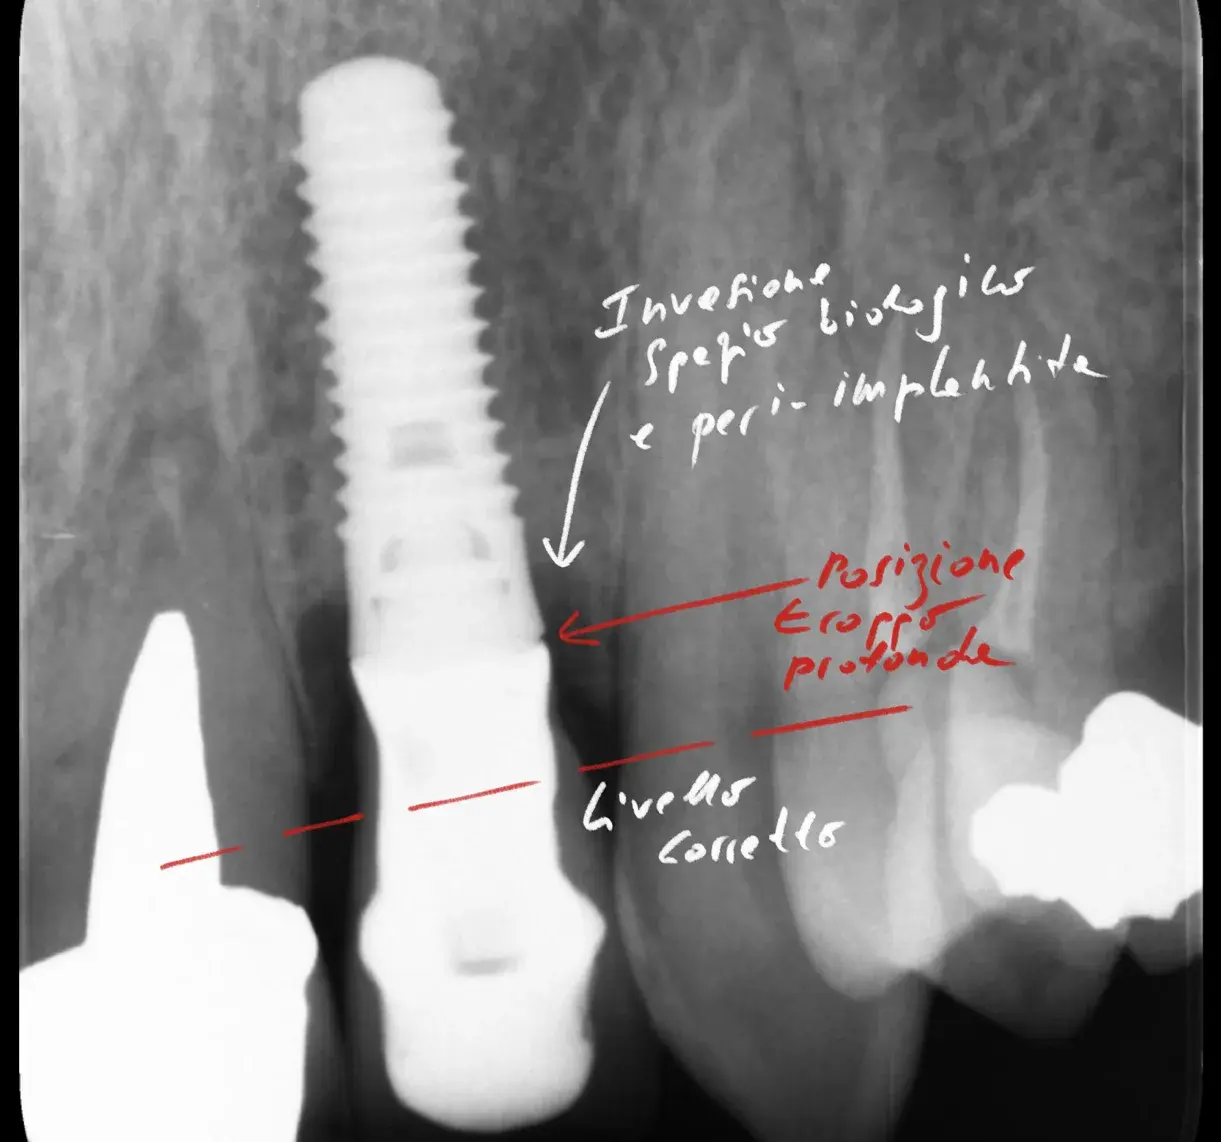

Bone-level, tissue-level, connessione conica: la profondità corretta cambia con il tipo di connessione. Perché sbagliarla causa riassorbimento osseo.

Un impianto mal posizionato causa perdita ossea di 0,25 mm ogni 10° di errore. Come riconoscere il problema, quando si può correggere e quando va rimosso.